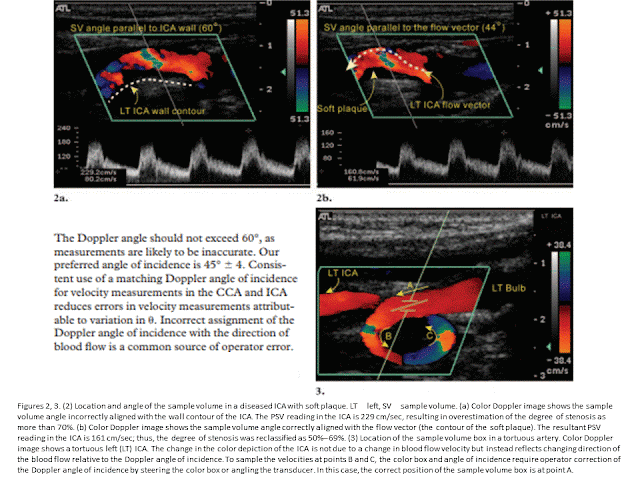

Ultrasonography (US) of the carotid arteries is a common imaging study performed for diagnosis of carotid artery disease. In the United States, carotid US may be the only diagnostic imaging modality performed before carotid endarterectomy. Therefore, the information obtained with carotid US must be reliable and reproducible. Technical parameters that can affect the accuracy of carotid US results include the Doppler angle, sample volume box, color Doppler sampling window, color velocity scale, and color gain. Important factors in diagnosis of atherosclerotic disease of the extracranial carotid arteries are the intima-media thickness, plaque morphology, criteria for grading stenosis, limiting factors such as the presence of dissection or cardiac abnormalities, distinction between near occlusion and total occlusion, and the presence of a subclavian steal. Challenges to the consistency of carotid US results may include lack of a standard protocol, poor Doppler technique, inexperience in interpretation of hemodynamic changes reflected in the Doppler waveform, artifacts, and physical challenges. Hindrances in the classification of problematic carotid artery stenoses may be overcome by following a standard protocol and optimizing scanning techniques and Doppler settings.